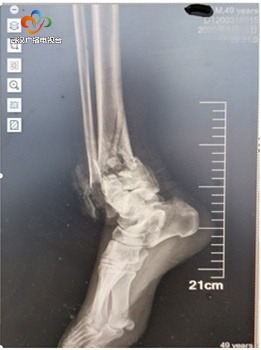

师傅家经营者一家小超市,昨天中午,赵师傅和爱人来到店面清理库存,打扫店面。没想到在清理仓库时,赵师傅爬上货架后时接了个电话,不小心从2米高处摔了下来。拍片显示患者右脚脚踝粉碎性骨折,碎成了8块需要立即手术.

一层洗手衣,一层防护服,一层手术衣,穿着3层“衣服”,戴着3层手套,头上戴着口罩和护目镜、面罩,当日手术医生严立凭借经验用6根克氏针将患者的碎骨一一固定。骨科手术不仅考验医生手尖的技术,还讲究力道,虽然手术时间不长,可一小时下来防护服成了“暴汗服”,手术台上的医生护士各个全身湿透。